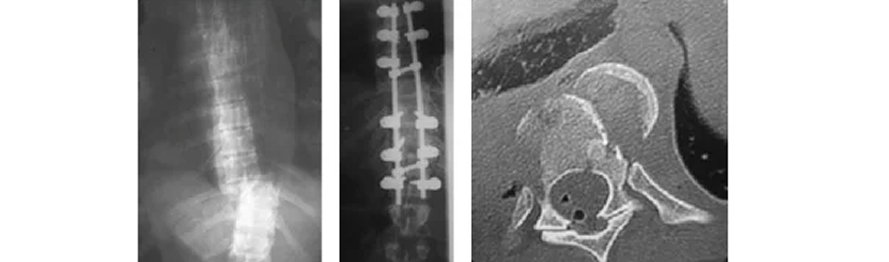

Na coluna vertebral as fraturas torácica e lombar são as mais freqüentes, correspondendo a cerca de 89% das fraturas. Sua distribuição ao longo dos segmentos torácicos e lombares é muito heterogênea e está diretamente relacionada com as diferenças anatômicas e funcionais desses segmentos e com o mecanismo do trauma. Na coluna cervical, as principais causas de fratura são acidente motociclístico, mergulho com trauma craniano e quedas.

As fraturas podem ainda ser classificadas como patológicas, quando há alguma doença óssea que leve à uma fragilidade vertebral, facilitando ao aparecimento de fraturas mesmo com mínimos traumas.

O tratamento dessas fraturas sofreu grandes modificações nestas últimas décadas, e o conhecimento das características individuais de cada tipo de fratura tem influenciado a estratégia terapêutica, conservadora ou cirúrgica.

O principal objetivo do tratamento é garantir a estabilidade, os movimentos e a função da área lesada. Nos últimos 20 anos observou-se um grande aumento na indicação de tratamento cirúrgico nas fraturas da coluna, esquecendo-se os resultados satisfatórios obtidos com o tratamento conservador.